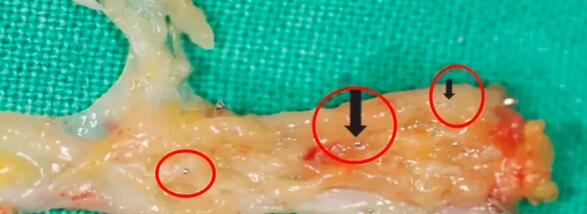

最后手術切除的肉芽里

還有細小閃亮的水銀滴

▼

圖片來源:J Hand Surg Asian Pac Vol. 2017 Dec;22(4):519-522.